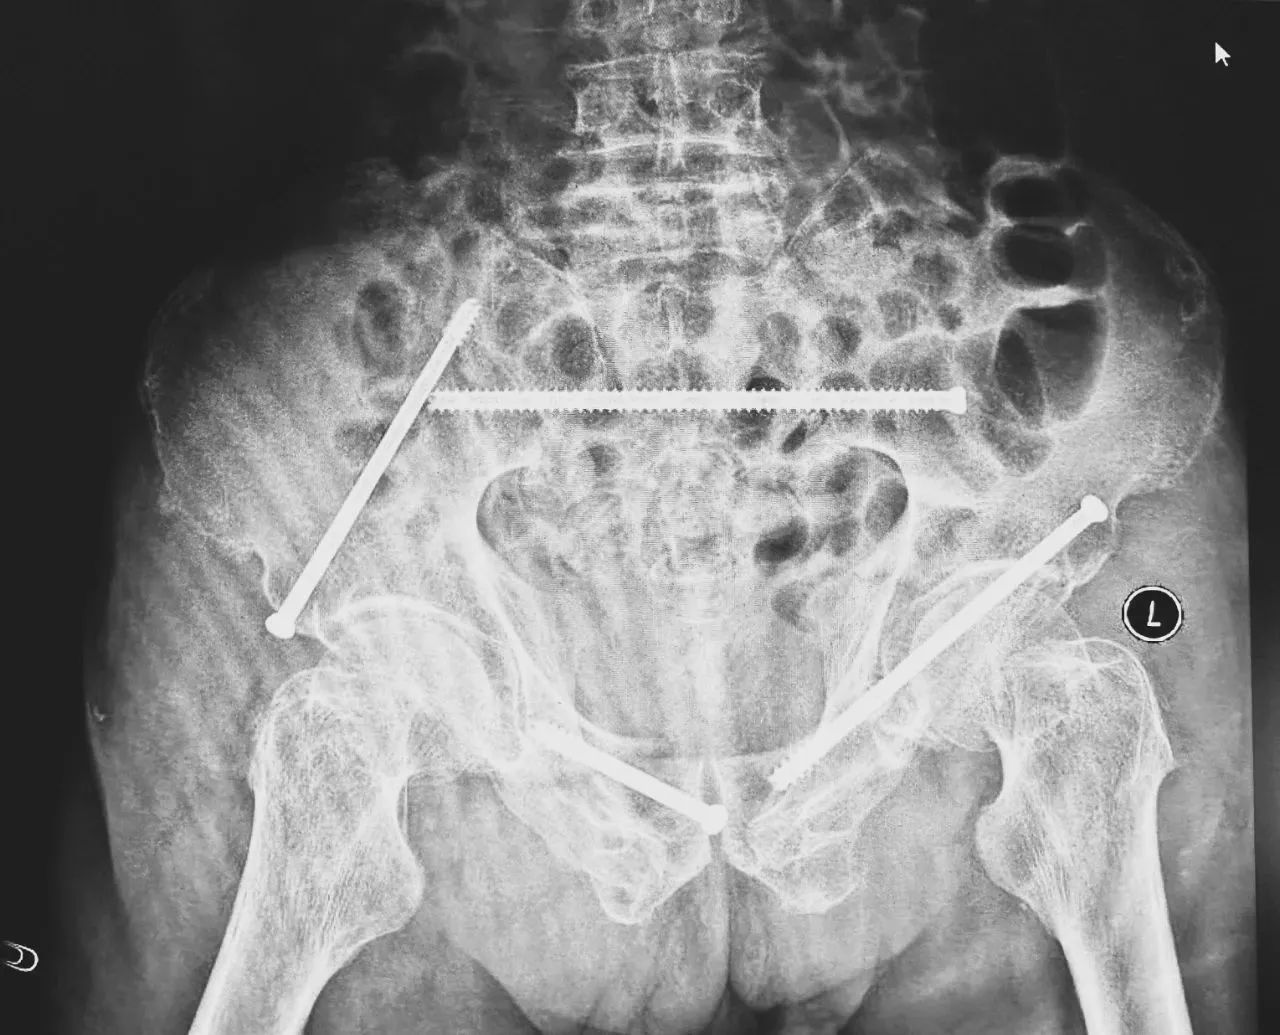

術(shù)前影像學(xué)顯示,患者的左側(cè)骶骨骨折,右側(cè)恥骨骨折、髂骨骨折,骨盆骨折分型為C型,老年脆性骨盆骨折分型為IV型,是極度不穩(wěn)定型的前環(huán)骨折和雙側(cè)后環(huán)骨折。所幸沒有明顯的骨盆出血或內(nèi)臟損傷的表現(xiàn)。

無影燈下,智能骨科團(tuán)隊(duì)將患者示蹤器,放在左側(cè)髂前上棘,使用術(shù)中三維影像設(shè)備獲取骨盆的三維圖像,掃描結(jié)果傳輸至機(jī)器人導(dǎo)航系統(tǒng),完成螺釘置入的位置和走形,并在機(jī)器人的引導(dǎo)下分別置入4枚通道螺釘。置入后再次進(jìn)行CT掃描驗(yàn)證,證實(shí)導(dǎo)針精確置入。

在骨科手術(shù)機(jī)器人毫米級(jí)精度的引導(dǎo)下,這項(xiàng)原本高難度、高風(fēng)險(xiǎn)的手術(shù)變得更加精準(zhǔn)高效。手術(shù)共計(jì)耗時(shí)1個(gè)半小時(shí),術(shù)中出血不到20毫升,每枚螺釘置入位置的切口長(zhǎng)度約1.5厘米,完美達(dá)到了預(yù)期。術(shù)后,王大爺安全返回病房。

術(shù)后第二天,醫(yī)生團(tuán)隊(duì)復(fù)查X片顯示螺釘植入位置非常滿意,骨折基本達(dá)到穩(wěn)定復(fù)位,同時(shí),復(fù)查的全血細(xì)胞計(jì)數(shù)中,血紅蛋白指數(shù)為102g/L。術(shù)后第三天,在智能骨科病房護(hù)理團(tuán)隊(duì)及康復(fù)師的指導(dǎo)和護(hù)理下,王大爺可以坐立在床上。術(shù)后第四天,王大爺迎來了出院日,“得虧有了這么先進(jìn)的醫(yī)療技術(shù),讓我還能下地行走,謝謝你們!”

螺釘植入位置非常滿意